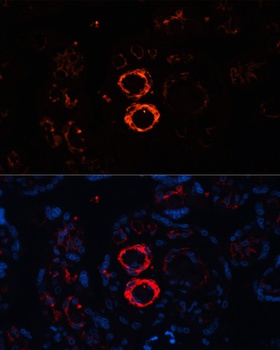

IHC: Formalin-fixed, paraffin-embedded human Leiomyosarcoma stained with SMMHC antibody (MYH11/923).